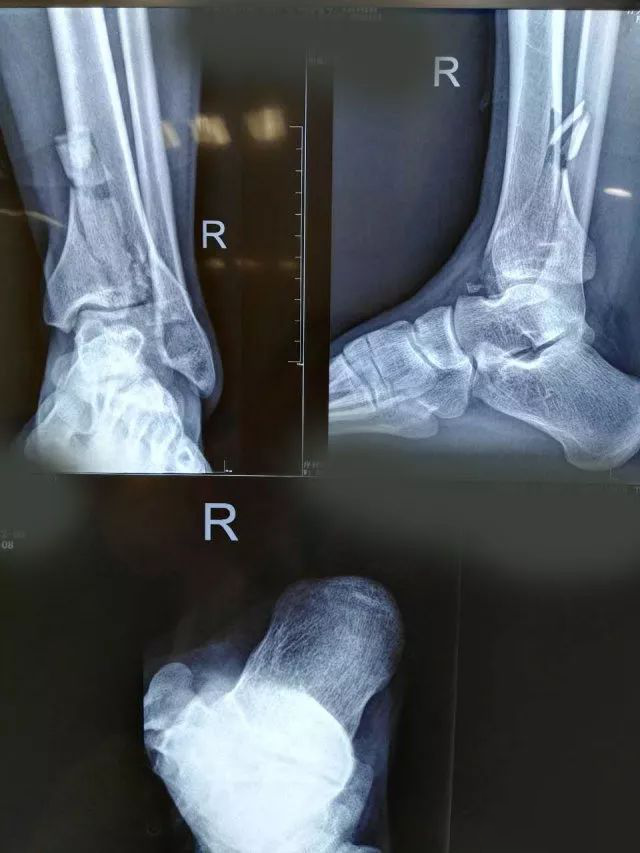

一起来看一个病例:男,20岁,摔倒右踝3天,体格检查示右小腿下段肿胀压痛,活动受限,运动感觉可,诊断为右侧 Pilon骨折。X片及CT三维图如下,欢迎投票并在评论区附上理由。